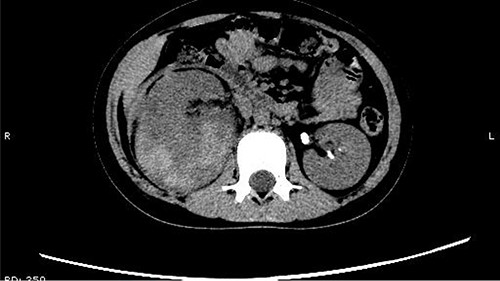

The patient was confined to bed, fasted and prescribed a daily intravenous infusion of cefazolin sodium pentahydrate, 2.0 g for 10 days. CT showed some irregular high-density shadows were present in the left renal pelvis (Fig. 1), and a small strip of high-density shadow was apparent in the bladder cavity (Fig. 2). Blood tests showed no abnormality in serum calcium concentration. Cefazolin sodium pentahydrate was discontinued immediately.

A small strip of high-density shadow was present in the bladder cavity.